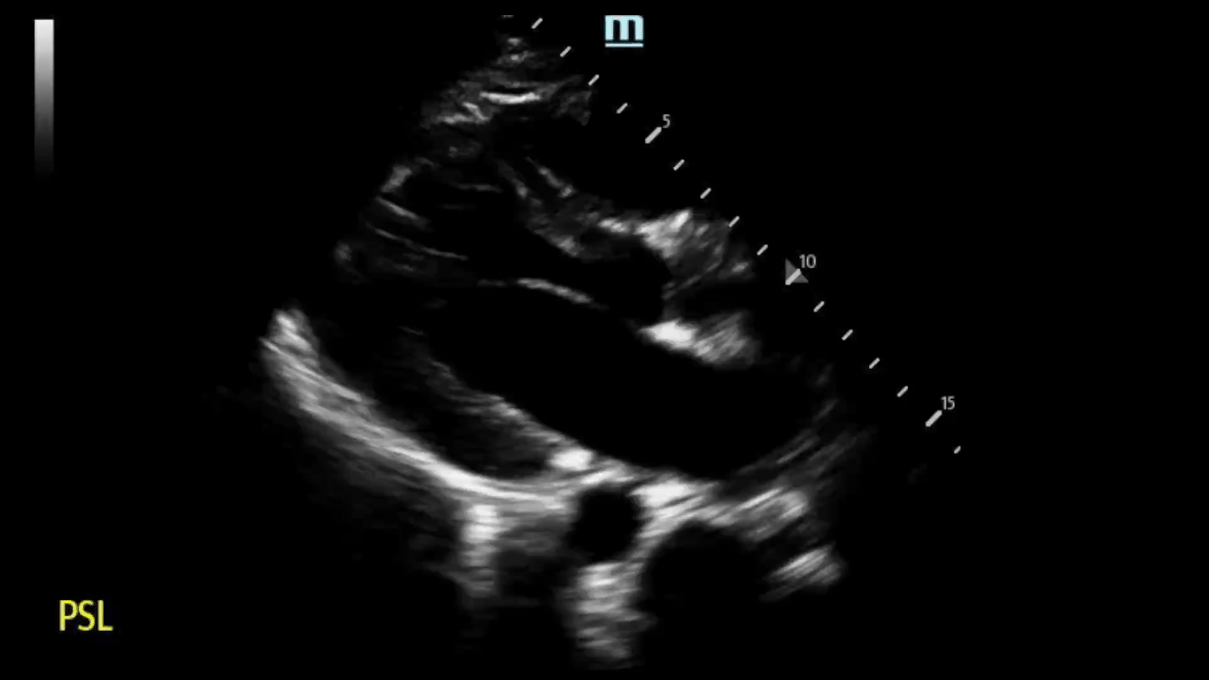

Finding #1: Unexplained LV wall thickness of > 15 mm at any segment during diastole

• View: PSL View

• “Unexplained” meaning not due to a history of longstanding hypertension, aortic stenosis, a highly competitive athlete, or other etiologies

• Typically there is focal thickening - can be basal, mid-septal, mid-ventricular, apical

Left image shows septal and LV wall thickening, consistent with HCM. Right image is of a normal heart.

PSL View:

Based on our measurement, the interventricular septal-to-LV wall thickness ratio would be 16.5 mm/32.5 mm = 0.51. This is not consistent with HCM. However, the LV wall thickness is 32.6mm, which would be consistent with HCM.